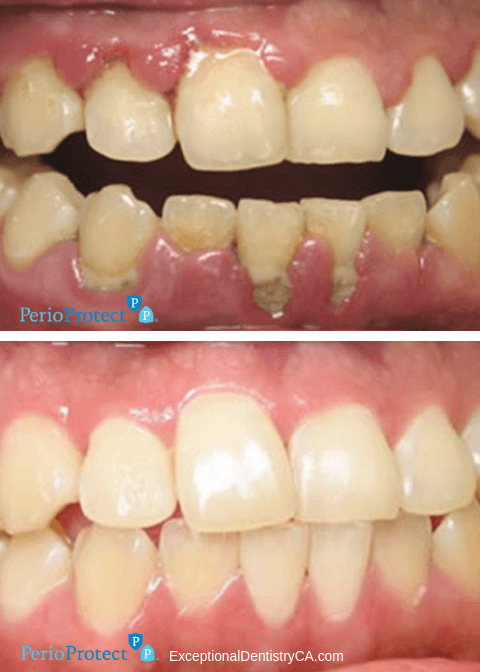

The Perio Protect Method was devised as a way to treat gum infections without surgery and with results. It resolves infection while reducing gum disease-causing bacteria, making way for long-lasting results. Treating gum disease with the Perio Protect Method has been shown to reduce the presence of the most damaging pathogens in your gums by up to 90%. Gum disease treatment helps reduce the risk of heart disease, type 2 diabetes, respiratory disease, Alzheimers disease, colorectal cancer and pre-term births and low birth-weight babies.

Studies have traced pathogens that lead to gum disease to the same pathogens known to cause other systemic inflammation and illness. Perio Protect is designed to reach the places where bacteria thrive below the gumline, in your periodontal pockets. Perio Protect involves a patented prescription antimicrobial medication that helps kill those pathogens and remove bacteria and plaque in periodontal pockets, where brushing, flossing and even mouth wash cannot reach. The antimicrobial medication also helps whiten teeth and freshen breath.

After your consultation, our dentist will provide you with custom-made Perio Trays that you can use at your convenience at home. Perio Trays are designed with a patented seal to place and hold medication at the gumline where it will be most effective, so there is no mess and no fuss. You can treat gum disease without disrupting your schedule.

Killing bacteria is a battle of persistence. These gentle, convenient trays carry out their duty while you kick back and stream your favorite show, take a shower or walk your dog. It is a non-invasive option before surgery or a chance to decrease the need for repetitive scaling procedures.